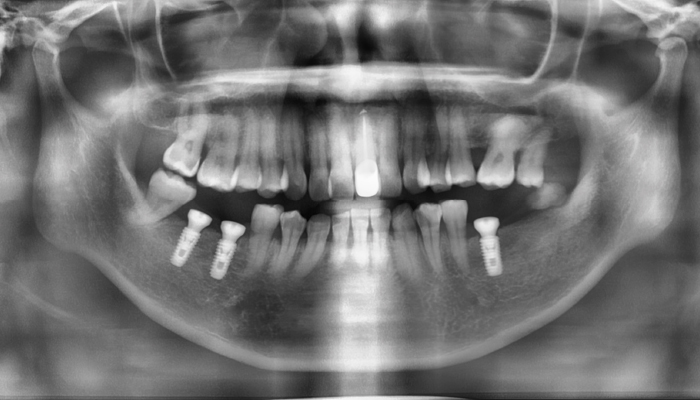

상악동거상술 전후 사례

• 식립 전

식립 후